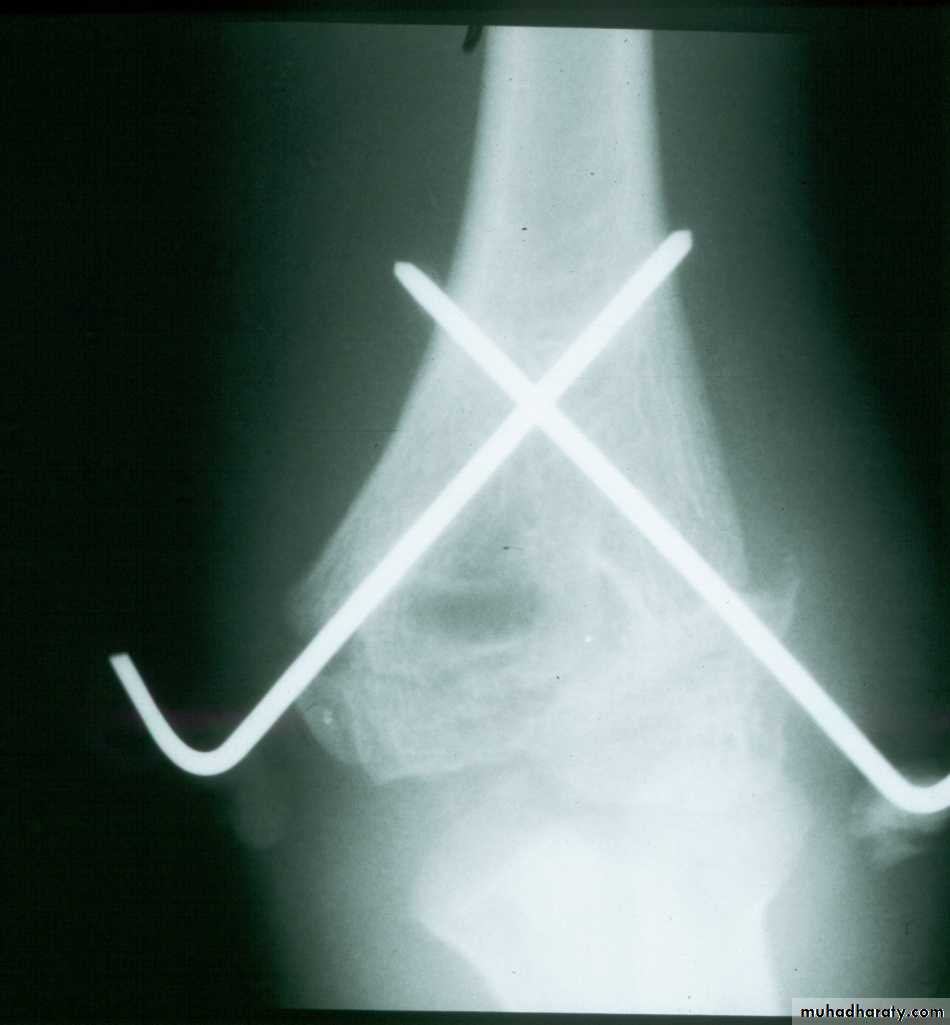

Percutaneous

pin

fixation

If a cast is inadequate,

then what is the standard for maintaining the reduction?

Medial-lateral

pins

In what manner may the pins be used?

Two lateral

pinsPins crossing at the

fracture lack stability

*Cheng J, Lam T, Shen W.

J Orthop Trauma 9:511,1995.